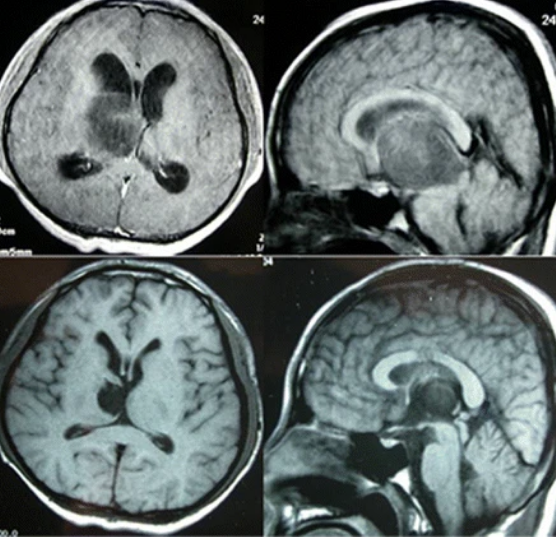

基底节区胶质瘤,是指生长在基底节区或附近的胶质瘤。基底节(basal ganglion)又称基底核(basal nucleus),位于近大脑半球底部的白质中,是大脑半球深部规模较大的核团,位于基底节区的胶质瘤往往会影响到患者的肢体运动功能。胶质瘤历来以高死亡率被冠以“病魔”的称谓,其主要由于胶质瘤被发现时,已经发展为恶性的高级别胶质瘤,难以治疗。

在过去的几十年里,神经外科以及整个医学领域所经历的较大变化之一,就是使用高科技成像技术,以清晰和详细的方式观察人体内部。核磁共振成像、CT扫描、超声波和PET扫描使神经外科医生能够检测和诊断各种各样的大脑和脊椎问题,大大减少了“探索性手术”诊断的需要。

INC国际神经外科专家表示,对于位于大脑深处的基底节胶质瘤,早期发现、及时治疗是存活的关键。如果能在早期发现胶质瘤,患者不必过于恐慌,胶质瘤能在早期发现是幸运的,这意味着,这时候胶质瘤还是低级别良性胶质瘤,患者通过科学的治疗有很大希望将其完全治好。